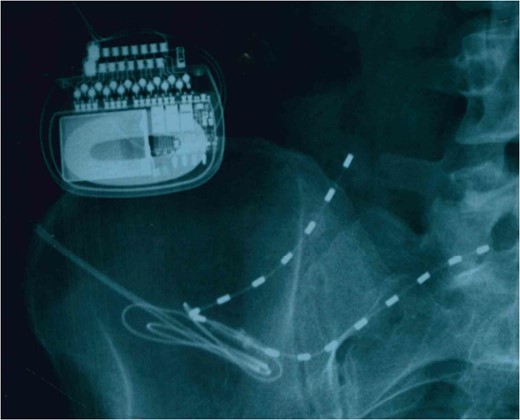

To the best of our knowledge, PNfS has not been documented for the treatment of abdominal CRPS. PNfS has been used for chronic pain with a promising outcome notably in three cases of chronic abdominal pain [7–9]. In this case, she experienced >90% pain reduction from the PNfS therapy during the trial of SCS versus PNfS. In the 5-year follow-up period, after permanent PNfS implantation, she continues to receive >60% of pain relief without any PNfS-related complications.